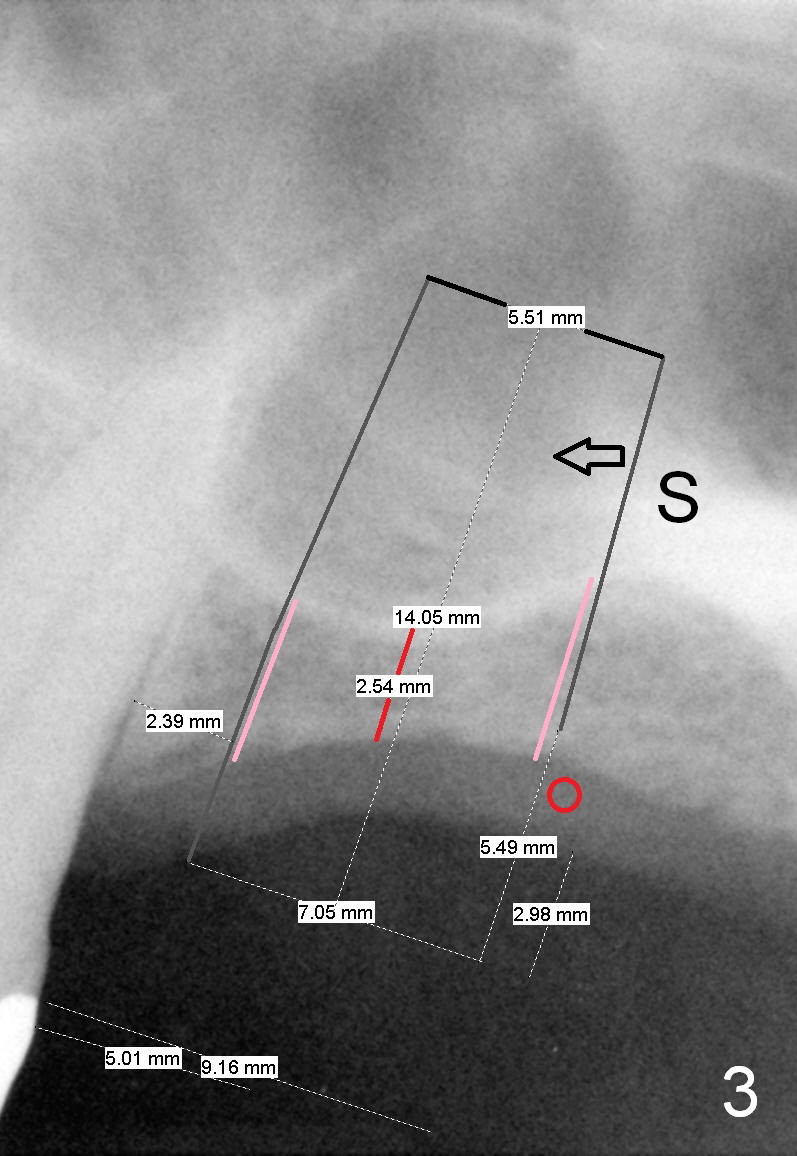

A 60-year-old man requests implant at the site of #14 (Fig.1,2, opposing a natural tooth (Fig.7)). Although bone height is limited, bone density appears high with sinus septi (S and arrowheads). The ridge seems to be wide clinically; implant will be as wide as possible. An envelop incision will be made to get the best visibility (as compared to tissue punch). At entry point, the bone height is 2.5 mm (Fig.3 red line); as the implant or osteotomy diameter increases, bone contact enhances (pink lines). If lateral window approach is adopted, a longer implant will be chosen (14 mm in Fig.3 vs. 11 mm in Fig.4, both tissue-level). The stronger distal septum may deviate the apical portion of the longer implant (Fig.3 arrow).

Another set of choice will be bone-level implants (SM and UF). The advantage of the former is its taper; the difference of the base and apex diameter is 1.1 mm (Fig.5 vs. 0.6 mm for UF (Fig.6)). It appears that a smaller parallel-walled drills can be used for the former (underprep) so that primary stability is more easily achievable. But according to the manufacture, the design of the latter allows the threads to be more aggressive. The surface treatment of the latter is more advanced (hybrid sand blast & acid etched vs. resorbable blast media; osseointegration occurs quicker for the latter). Which implant is finally chosen?